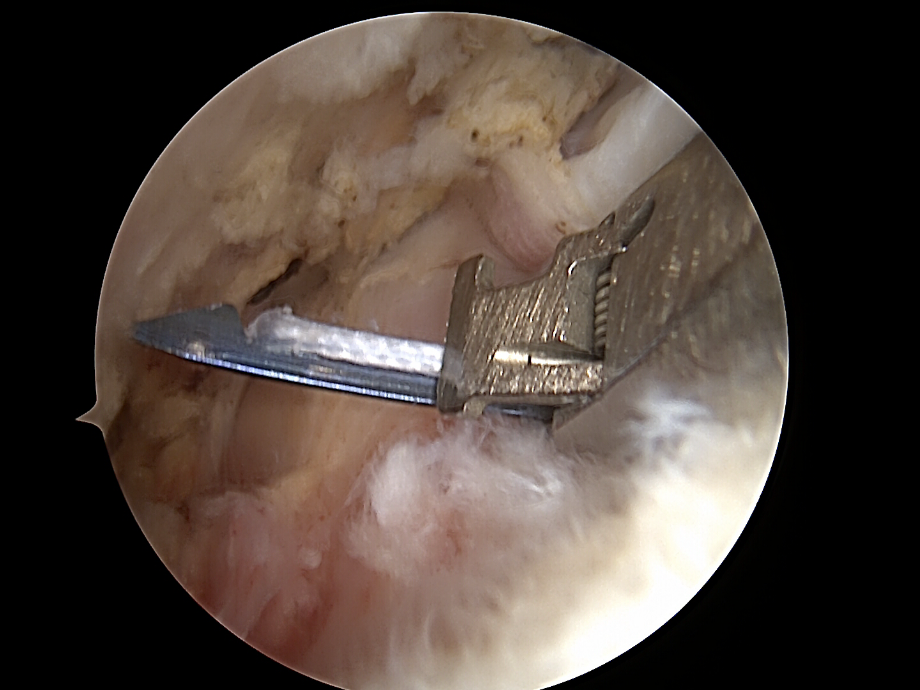

Darstellung und Mobilisierung der Sehnenstümpfe

• Débridement von degeneriertem Gewebe.

• Mobilisierung der rupturierten Sehne (meist Supraspinatus, ggf. Infraspinatus/Subscapularis).

• Darstellung des Ansatzbereichs am Knochen (Tuberculum majus/minus humeri).

• Glättung und Anfrischen des Footprints (Sehnenansatzstelle) zur Förderung der Knochen-Sehnen-Heilung.